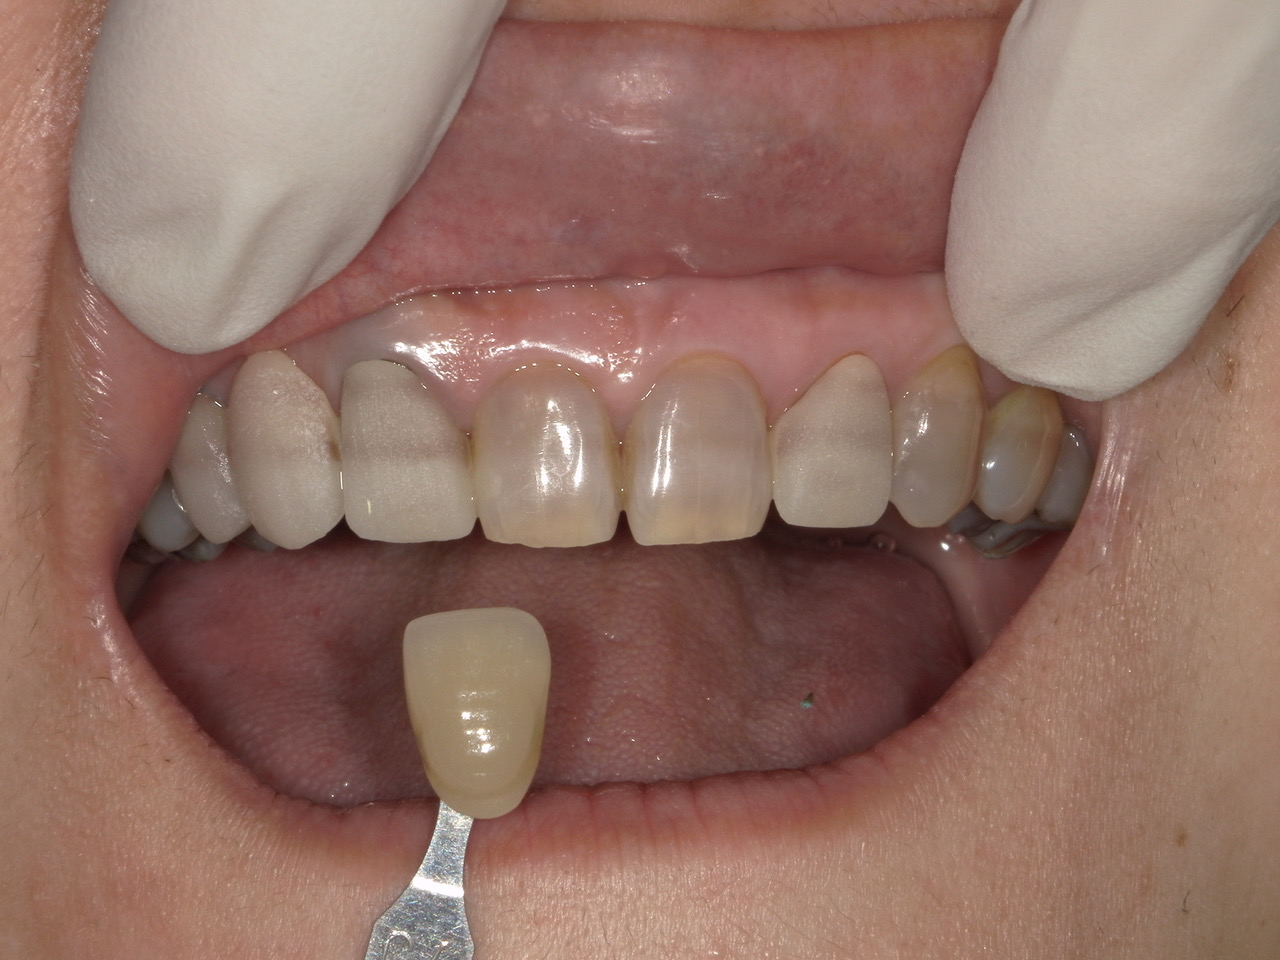

前歯の被せ物をきれいにしたいとのことで来院された患者様(50代・女性)です。

もともと上の左右に硬質レジン前装冠と呼ばれる保険適応で製作された被せ物及びブリッジが装着されておりましたが、周囲歯牙との色調の不一致、被せ物の不適合を認めました。

同時にテトラサイクリン系抗生物質によると考えられる先天性の歯牙の変色が認められました。

今回の患者様はホワイトニングをご希望されなかったため、周囲の歯に合わせた被せ物をジルコニアをベースとして審美性の高い陶材を表層に用いる2層構造のセラミックを当院で製作することとなりました。

<試適時>